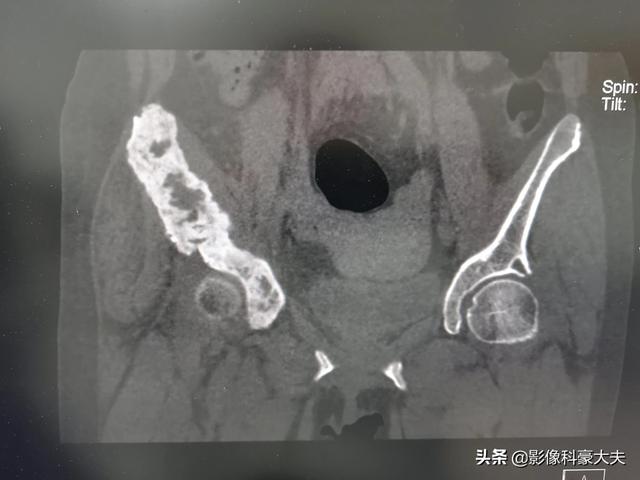

この患者は股関節痛に悩まされており、大腿骨頭の壊死が疑われた。その結果、骨盤のCTで骨転移が見つかり、さらに検査を進めた結果、進行した肺がんが見つかった。

骨転移が起こる最も一般的な部位は、腰椎、骨盤、肋骨、頭蓋骨、大腿骨である。

骨に転移しやすいがんがありますが、骨転移の見分け方は?肺がん、肝臓がん、乳がん、前立腺がんなど、がんは転移しやすく、正常な組織を破壊しますが、転移部位として多いのが骨です。私たちの仕事でも、骨の痛みで受診し、検査の結果、がんの骨転移と診断されることがあります。前立腺がんの骨転移(黒丸部分)